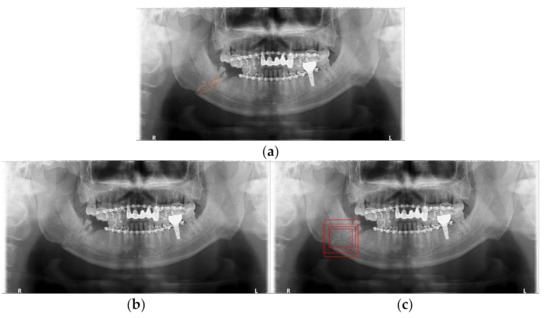

Mandibular fracture is one of the most frequent injuries in oral and maxillo-facial surgery. Radiologists diagnose mandibular fractures using panoramic radiography and cone-beam computed tomography (CBCT). Panoramic radiography is a conventional imaging modality, which is less complicated than CBCT. This paper proposes the [...] Read more.

Mandibular fracture is one of the most frequent injuries in oral and maxillo-facial surgery. Radiologists diagnose mandibular fractures using panoramic radiography and cone-beam computed tomography (CBCT). Panoramic radiography is a conventional imaging modality, which is less complicated than CBCT. This paper proposes the diagnosis method of mandibular fractures in a panoramic radiograph based on a deep learning system without the intervention of radiologists. The deep learning system used has a one-stage detection called you only look once (YOLO). To improve detection accuracy, panoramic radiographs as input images are augmented using gamma modulation, multi-bounding boxes, single-scale luminance adaptation transform, and multi-scale luminance adaptation transform methods. Our results showed better detection performance than the conventional method using YOLO-based deep learning. Hence, it will be helpful for radiologists to double-check the diagnosis of mandibular fractures. Full article

Show Figures